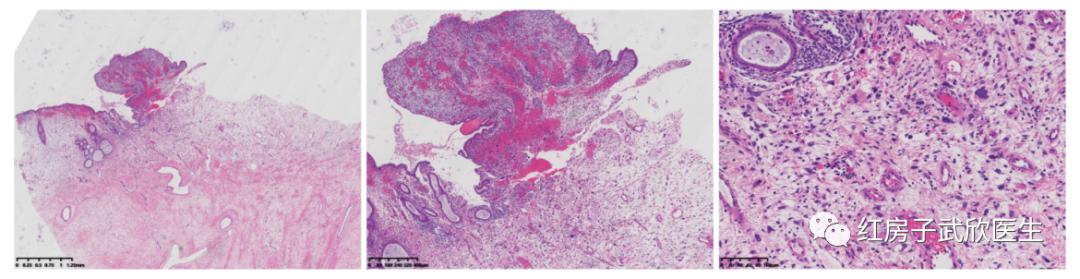

入院后完善相关检查,排除手术禁忌症,于2018-02-11在全麻下行阴式阴道内肿物切除术。术中见宫颈口一直径约8*7*6cm3肿物,成分叶状,部分囊性、质实、胶冻状。探针探蒂宽约0.8cm来源于宫颈内口2点位置。超声刀滑至肿物蒂部,分次凝切,摘除肿块。术中冰冻:(阴道内肿物)镜下见肿块内由间叶源性成分及腺体组成。术后病理回报:(阴道内肿物)宫颈胚胎性横纹肌肉瘤。免疫组化:MyoD1(核)(+),Myogenin(局灶+),P53(散在+),Ki-67(70%+),Myosin(个别细胞+),SMA(-),Desmin(+),Caldesmon(-),CD10(+),EMA(-),CCND1(+)。

病理结果出来后对小叶无疑是一个致命的打击,她还那么年轻,生活才刚刚开始,她无法面对眼前的一切,走投无路的她再次找到了武欣教授。武教授告诉她,国际上该病例主要手术方式为全子宫加双侧附件切除术,病灶接近宫颈时行广泛全子宫切除术加盆腔淋巴结清扫术,术后辅助化疗或放疗。考虑小叶19岁,有强烈保留生育功能要求,于是武教授给她组织了多学科会诊。病理科讨论后认为生发层下的间质疏松,散布短梭形的肿瘤细胞,没有明显的异型。仅部分区域肿瘤细胞出现显著的异型性,一些有大的单个核仁。推断增殖活跃的肿瘤细胞呈小区域性聚集。影像科行PET-CT全面评估,结果未见异常。鉴于患者19岁,有强烈保留生育功能需求,综合现有文献,结合该患者病理,细胞恶性程度不高。决定行宫腔镜下病灶根蒂部切除+前哨淋巴结活检,已判断患者是否存在残留病灶及转移可能。